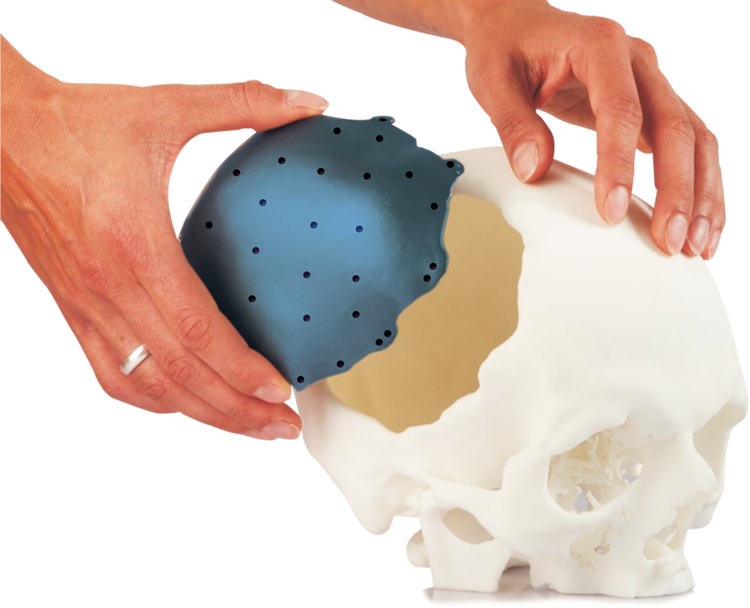

- Custom Made Cranial Implant

- Craniofacial Implants

- Better anatomic fit

- Complex structures possible

- Reduced operating time

- Satisfying aesthetic results

CONSTRUCTION OF A 3D-IMPLANT MODEL

On the basis of the virtual 3D-patient model an implant model is constructed. After consultation between you, the treating physician, and our technical designers, you determine the final implant shape. The consultation can take place either via telephone or via E-mail. If necessary we send you also real 3D- model for the implant planning.

A perfect fit implant as per your patient anatomy

PATIENT SPECIFIC IMPLANTS

Patient-specific implants are designed and produced according to patient-derived CT data for excellent reconstructive results. Our main products are patient-specific implants for the brain- and face-skull areas. These patient-specific implants can, for example, become a necessity after trauma, tumour surgeries, surgery accesses. This new procedure allows us to create implants that are custom-made for every patient.